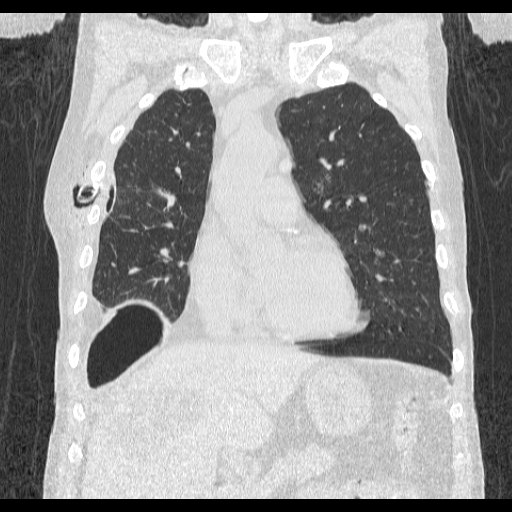

# Image source: Case courtesy of Tariq Walizai, Radiopaedia.org, rID: 184833

# https://radiopaedia.org/cases/184833?lang=us

image = Image.open("path-to-resources/chest-tube.jpg").convert("RGB")

seed_points = [[135,235],

[360,215],

[115,335]] # (X,Y) coordinates of points

color_values = [(255, 0, 0),

(0, 255, 0),

(0, 0, 255)] # (R, G, B)

tolerance = 2